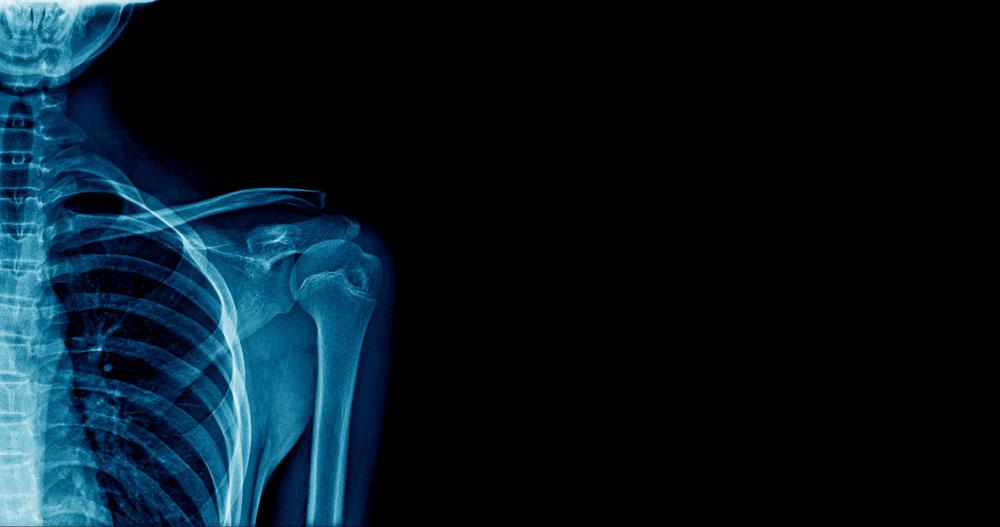

X-ray